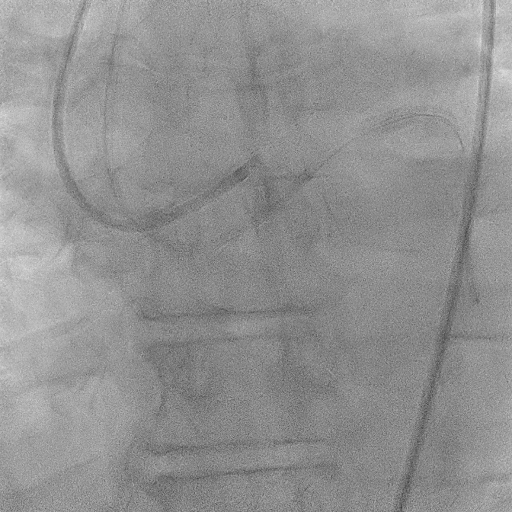

The procedure commenced with EBU 3.5/6F catheter and CTO wire with microcatheter. Managed to cross the lesion and changed to workhorse wire. Proximal LAD ISR predilated with SC balloon 2.0/15mm. CTO at mid segment predilated with same balloon. However, noted perforation at mid LAD after predilatation. We used the same balloon to tamponade the perforation and attempted to wire down distal LAD with another wire but failed. Right femoral puncture was performed and another EBU3.5/6F was used. The ping pong technique was used in which another workhorse wire to distal LAD when tamponade balloon was deflated. However, the covered stent was unable to cross the proximal LAD. Proximal segment was then predilated with NC 2.5/15mm, yet still unable to advance the covered stent. Subsequently, guide extension GuidePlus II was used and managed to advance covered stent 2.5/20mm. Tamponade balloon was then removed and covered stent deployed at perforation site. We proceeded with drug coated balloon angioplasty to proximal-mid LAD using DCB 3.5/20mm. Patient was stable and bedside echo revealed minimal pericardial effusion only